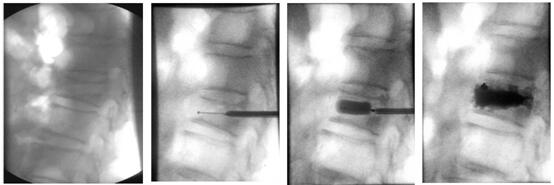

下面帶大家了解椎體成形術是怎樣做的!

患者俯臥位在手術床上,透視標記骨折椎體;

穿刺點局部麻醉,根據定位將穿刺錐穿入骨折椎體;

透視確定穿刺錐進入骨折椎體后,建立工作通道;

等待15分鐘骨水泥凝固硬化,手術結束。病人即刻疼痛消失,術后第一天可以下床活動。